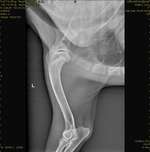

Unser kleiner Robby , Yorkischer Terrier, ist jetzt 7,5 Monate. Seid er ca.5 Monate jung war , denken wir befindet er sich im Zahnwechsel. Wir haben ihn mit 10 Wochen bekommen und seid dem 3.Tag bei uns schlief er komplett Nachts durch. Nach seinem 5.Monat hat er unruhige Nächte. Erst ...